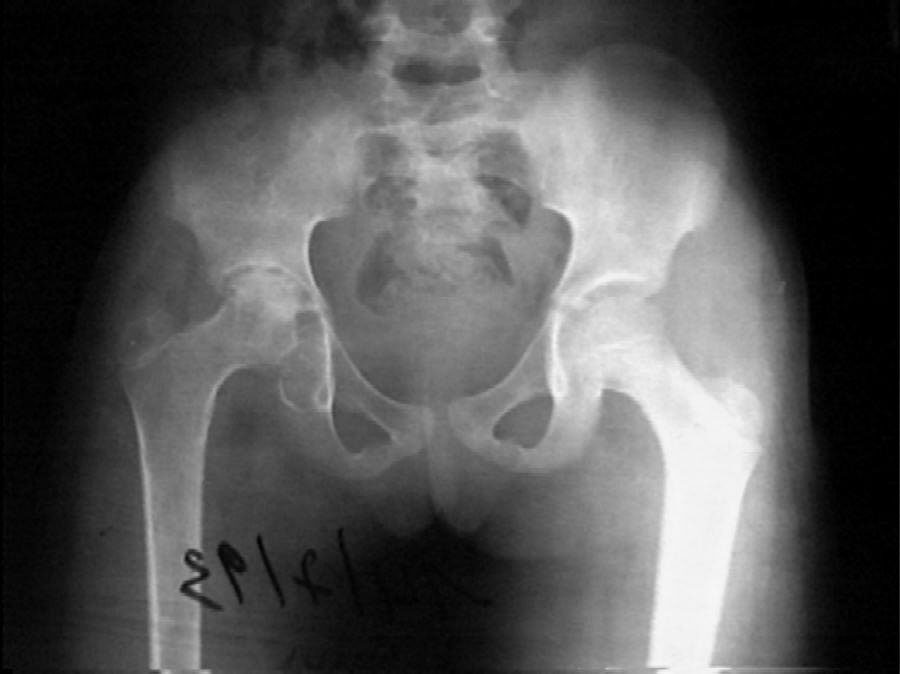

2 year followup xray - Click to enlarge.